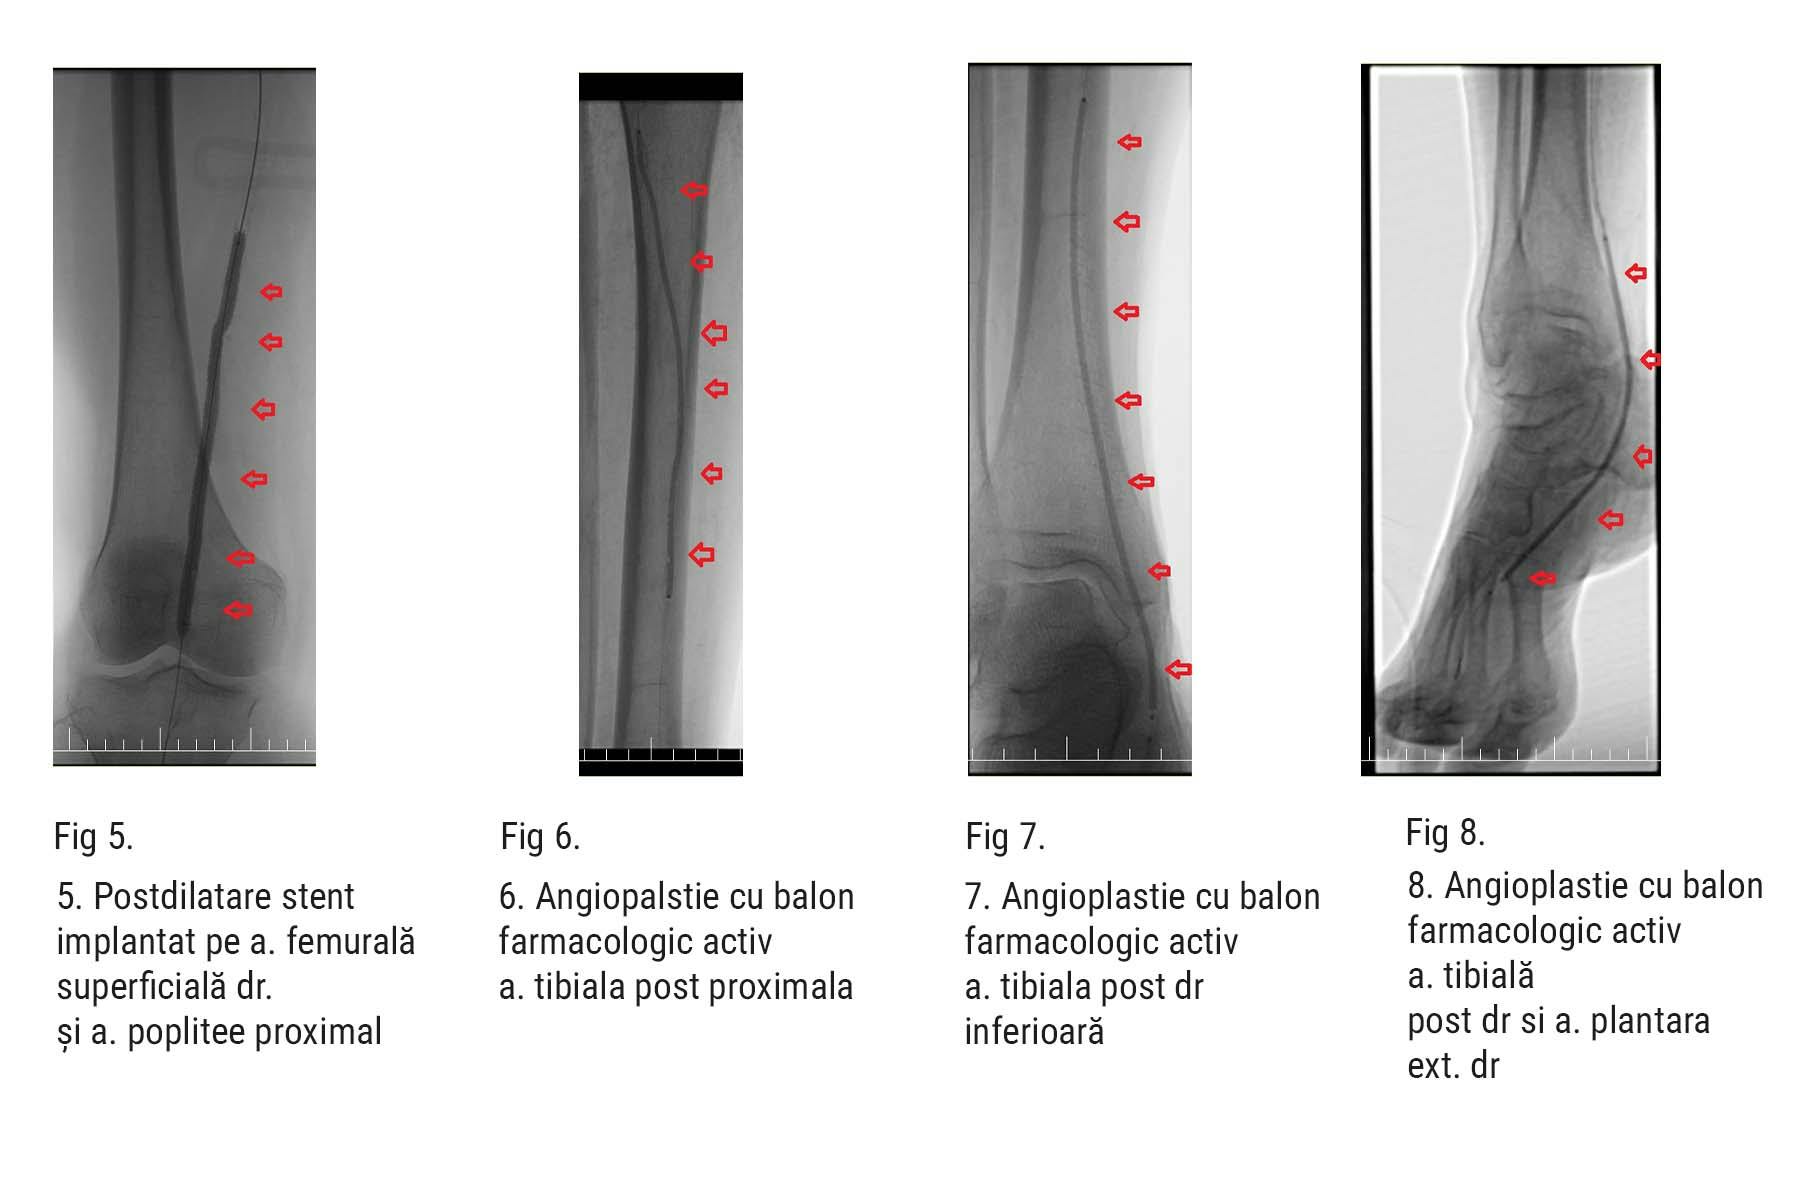

După ce a fost diagnosticată cu ocluzie arterială severă (blocaj), în urma unei ecografii doppler arterială la internarea în spital efectuată de dr. Alexandra Postu, medic primar cardiolog, pacientei i-a fost recomandată procedura dezobstrucție periferică și angioplastie. Acest tratament a presupus deschiderea arterelor blocate și inserția a două stenturi pentru a menține arterele deschise. În plus, s-a folosit un balon special, farmacologic activ, pentru a restabili și a menține fluxul sanguin în artera tibială posterioară. În imaginile angiografice de mai jos, poți observa vasele de sânge îngustate care nu permiteau sângelui să circule și să irige corespunzător țesutul piciorului.

Intervenția efectuată de dr. Nicolae Cârstea, medic cardiolog interventionist cu experiență vastă în dezobstrucțiile periferice, a fost un succes, iar circulația sanguină în picior a fost îmbunătățită. În doar câteva zile, pacienta a început să simtă ameliorarea durerilor, iar riscul de complicații majore (cum ar fi amputarea) a scăzut semnificativ. Iar aspectul membrului la o lună după intervenție arată beneficiile acestei proceduri.